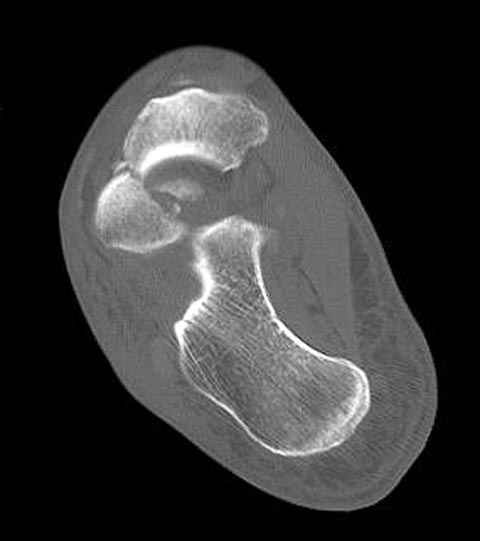

В декабре у меня был пациент с политравмой и аналогичным повреждением тарана с подвывихом в таранно- ладьевидном суставе, единственное отличие - отломок головки тарана был меньше по размеру и фрагментирован, поэтому его фиксация была невозможна.

Для доступа к задне-медиальному суставному фрагменту я выполнил косую остеотомию внутренней лодыжки у её основания -получается хороший доступ к голеностопу, адекватный обзор и возможность восстановить суставную поверхность. фрагмент фиксировал двумя 3,5 мм спонгиозными винтами с неполной резьбой, *утопив* головки винтов в кость. Аналогичная фиксация и двумя тягловыми винтами и внутренней лодыжки. \в качестве альтернативы для

Вывих в таранно-ладьевидном суставе удалось вправить с помощью Howard retractor, используя его в качестве рычага.Сегодня искал в рентген архиве

Повторный осмотр назначил через 2 мес с момента операции. Отдаленных наблюдений такого подхода у меня нет( достаточно редкий тип повреждений таранаHawkins II), но наблюдения в ближайшем послеоперационном периоде выглядели вполне прилично, на мой взгляд.